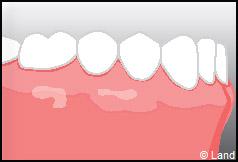

Outre la maladie parodontale, nous pouvons rencontrer des défauts de la gencive qui n’ont pas une origine infectieuse. Les plus fréquents de ces défauts sont les récessions gingivales, qui se traduisent par la migration de la gencive en direction de la racine (la racine est alors à nu).

Les conséquences de cette mise à nu de la racine dentaire sont multiples, le patient peut présenter une hypersensibilité dentaire et l’aspect de ces récessions peut être inesthétique. Dans ce cas, la chirurgie muco-gingivale est recommandée et elle peut se faire de différentes façons.